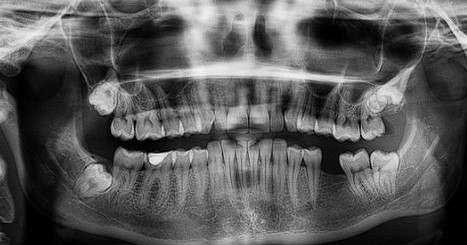

사랑니 발치 비용 대하여 총정리해보는 시간입니다.  미국에서는 보통 사랑니발치 비용이 1000$ 정도 한다고 하는데요. 이는 한화 130만원이 넘는 금액입니다. 하지만 대한민국에서 건강보험이 적용이 되죠. 발치 후 식사 및 안뽑으면 어떤지 알아볼게요.

일반적으로 사랑니가 나면서 통증이 생기는 이유를 알아보면요. 사랑니가 나서 아픈 이유 첫번째는 사랑니로 인하여 앞에 치아가 썩어서 발생하는 통증이 있습니다. 두 번째로 잇몸이 사랑니를 덮고 자라 올라와서 , 잇몸이 씹히거나, 세균이 번식하여 잇몸이 붇거나 하여 잇몸의 통증을 사랑니의 통증으로 착각하기도 합니다.

사랑니 발치 종류 비용

▪ 단순매복 (단순발치)

참고로 건강보험에서 사랑니가 앞의 치아와 평행하게 올라와 있는 경우에는 '단순매복' 이라고 하며, 단순매복같은 경우는 쉽게 발치하는 경우가 대부분입니다. 사랑니의 머리가 완전히 입안에 노출되어 있고 똑바로 나 있을 때 요런 경우의 발치 같은 경우는 본인 부담금 2~4만원 정도 비용이 발생합니다.

▪ 복잡매복

사랑니가 누워 있어서 그냥 뺄 수 없는 경우가 있는데요. 앞의 치아를 다치지 않게 , 누워있는 사랑니를 절단하여 깨끗하게 꺼내야 하는 경우가 있습니다. 일반치과에서 모두 가능하지 않으며 구강외과 전공의 또는 대학병원급에서 행해집니다. 의원급 기준으로 3~4만원의 본인 부담금이 발생하게 됩니다.

▪ 완전매복  (매복 사랑니 )

보통 완전 숨은 경우 발치가 필요없는데, 다음의 경우에는 발치가 필요합니다. 앞 치아의 뿌리에 영향을 주고 있거나 또는 반복적으로 잇몸이 붓거나 할 경우 완전히 묻혀있지만 발치를 해야하는 경우가 생깁니다. 완전매복의 사랑니를 빼야하는 경우에는 잇몸절개 그리고 뼈를 정리해 주어야 하고 아랫쪽 신경관을 잘 피하여 잘라서 꺼내야 합니다.

최상의 난이도를 자랑하는 완전매복 사랑니는 의원급 기준으로 4~5만원의 비용이며 , 추가로 ct촬영, 지혈제 사용 등 본인 부담 수가가 달라지기도 합니다. 최대 10만원 전후의 금액이 발생될 수 있어요.